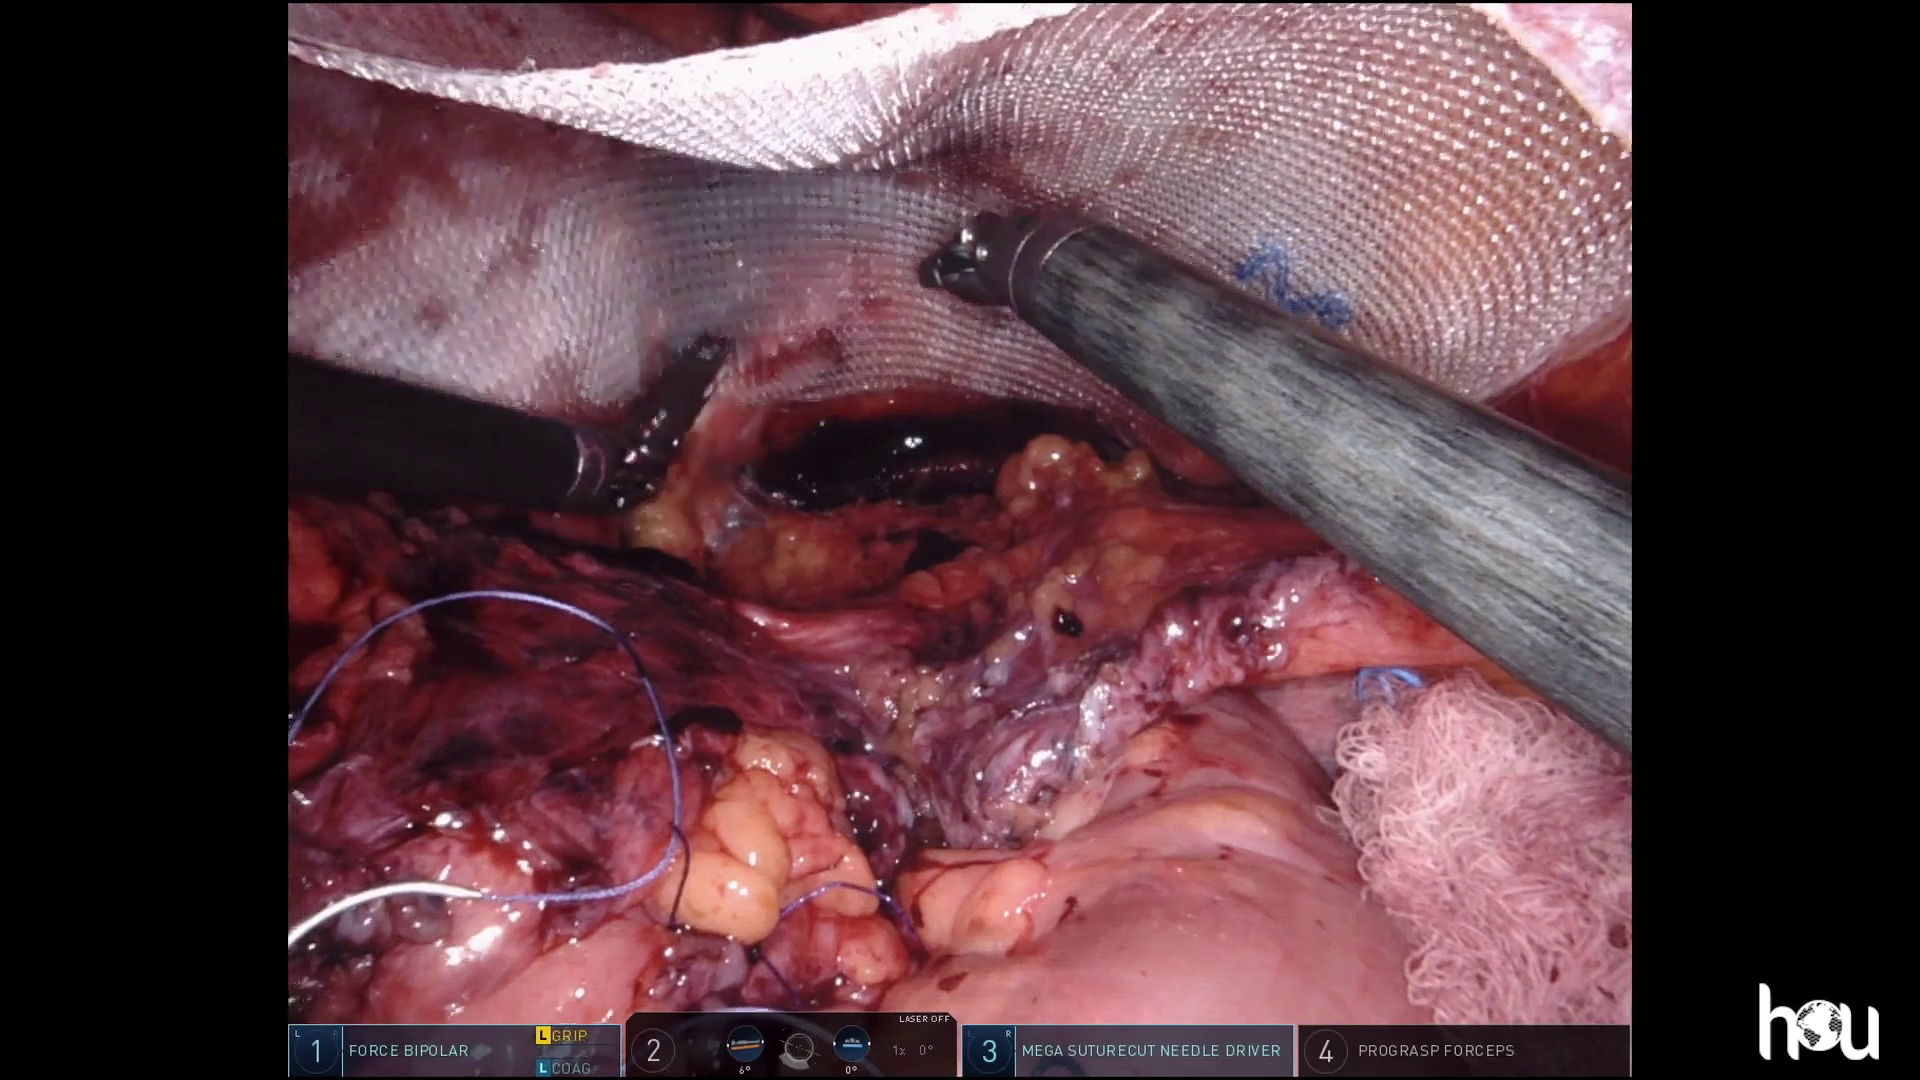

Dr. Malcher | Robotic repair of incarcerated inguinal hernia using CO2 asperation tip

Doctor(s): Dr. Malcher Description of of the case: Robotic repair of incarcerated inguinal hernia using CO2 asperation tip Products Used: Ventralight™ ST Mesh [...]